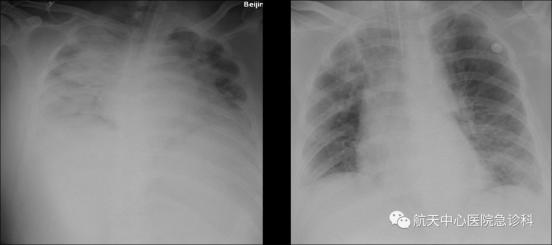

醫(yī)學(xué)上通常以喉為界,將呼吸道分為上下兩部分。當(dāng)發(fā)生下呼吸道感染時(shí),不要過于緊張和恐慌。上呼吸道包喉,下呼吸道包括支肺內(nèi)的各類支氣管。呼吸道感染可以分為兩種主要類型:上呼吸道感染和下呼吸道感...

白痰是痰液的一種性狀,咳痰為呼吸系統(tǒng)的局部癥狀之一。伴隨癥狀:呼吸道感染出現(xiàn)咳嗽癥狀后,如果出現(xiàn)呼吸困難等伴隨癥狀時(shí)也需要警惕白肺。但出現(xiàn)咳嗽的癥狀不一定代表患者有白肺的情況,也可能是由于...